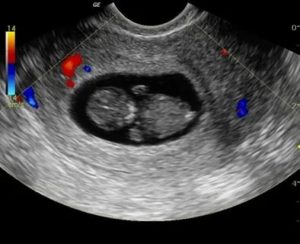

Признаки на УЗИ

Ультразвуковая диагностика – основной метод обследования. В первом случае о гибели ребенка свидетельствуют следующие характерные признаки:

- рост плодного яйца замедлен, а его диаметр не превышает 24 мм;

- отсутствуют какие-либо признаки зародыша;

- отсутствуют симптомы прогрессирования беременности.

Один из основных признаков – отсутствие сердцебиения на УЗИ